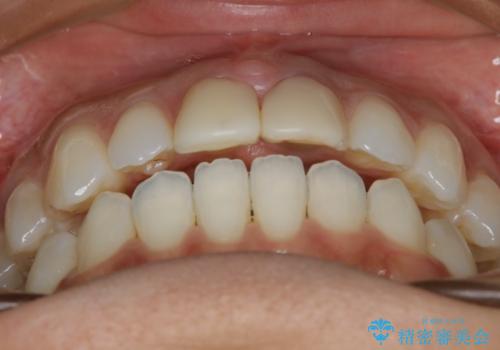

すきっ歯を治したい。インビザライン・ライトによる矯正治療

- 正中離開を気にされて来院された患者様です。

インビザラインでの治療を希望され、正中離開のみ治したいとのことだったので、インビザライン・ライト(片顎)での治療を選択しました。

インビザライン・ライトは枚数が少ないため歯の移動量に限界がありますが、短期間での治療が可能です。